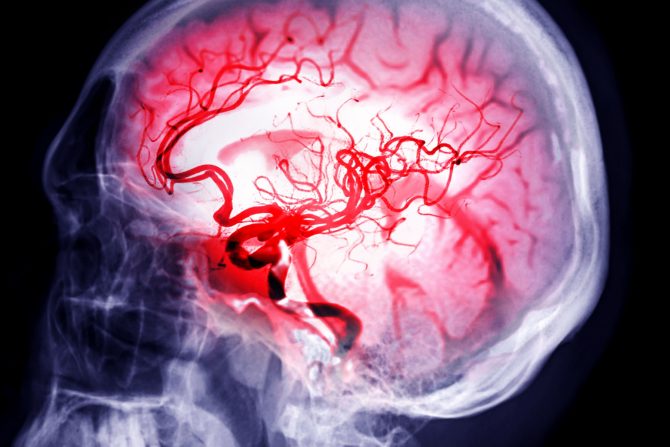

Moždani udar kod mladih i ljudi srednjih godina je sve češća pojava, a disekcija cervikalne arterije jedan od najčešćih razloga

Disekcija cervikalne arterije dešava se kada dođe do pucanja zida karotidne ili vertebralne arterije - krvnih sudova koji obezbeđuju mozgu krv bogatu kiseonikom. Kada dođe do disekcije cervikalne arterije istovremeno se javlja mogućnost za stvaranje krvnih ugrušaka, a potencijalne komplikacije uključuju moždani udar.

Disekcija cervikalne arterije dešava se kada naprsne, popuca jedan ili više slojeva tkiva krvnih sudova. Ovo stanje smatra se čestim uzrokom moždanog udara kod mladih i srednjih godina. Cervikalne arterije su grupa velikih krvnih sudova na vratu u koju spadaju karotidne arterije (koje snabdevaju prednji deo mozga) i vertebralne arterije (koje snabdevaju zadnji deo mozga i kičmu).

Sa disekcijom karotidne arterije dolazi do pucanja unutrašnjeg zida/obloge krvnog suda. Na mestu pukotine krv može da se zgruša, a ako se krvni ugrušak otkači, može da stigne do mozga, blokira  krvne sudove i ograniči protok krvi, što dovodi do ishemijskog moždanog udara.